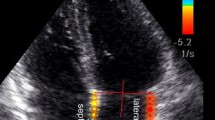

For evaluation of diastolic function septal motion and velocity-encoded flow measurements were assessed (Figs. 2, 3).

A 62-year-old male patient presenting with dyspnoea. Balanced-SSFP cine MRI (TR/TE 2.8/1.4 ms; flip angle 60°; slice thickness 8 mm, in-plane resolution 2.5 × 1.9 mm2; temporal resolution 48 ms) short-axis views (a) and four-chamber long-axis views (b). In systole the interventricular septum has a concave shape in relation to the left ventricle (a, curved black arrow), while during diastole the septum flattens (a, curved white arrow). Abnormal septal motion is also visible in the long chamber views (b, white arrows), as are a right ventricular thickened pericardium (b, arrowheads) and concomitant pleural effusions (*)

a Flow curves of velocity-encoded flow measurements at the mitral and tricuspid valves. Transtricuspid and transmitral flow curves of a 55-year-old male patient are shown with about same heights of the e-wave and the a-wave at both atrioventricular valves resulting in an e- to a-wave ratio of about 1. b Flow curve of a 42-year-old female patient. In contrast to Fig. 3a the amplitudes of the e-waves are higher compared with the a-waves. The e- to a-wave ratio at both the mitral valve and the tricuspid valve are between 1 and 2